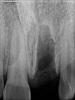

zood Опубликовано 5 февраля, 2010 Автор Поделиться Опубликовано 5 февраля, 2010 (изменено) ..скажите дорогие мои, как тут на снимочках? не все так плохо? Изменено 5 февраля, 2010 пользователем zood Ссылка на комментарий

Bier Опубликовано 5 февраля, 2010 Поделиться Опубликовано 5 февраля, 2010 по снимкам все очень даже не плохо. Можно имплантироваться 100% Ссылка на комментарий

Dr. Surkin Опубликовано 5 февраля, 2010 Поделиться Опубликовано 5 февраля, 2010 Ребят, я конечно понимаю, что КТ это вещь, но в данном случае она избыточна. Облучением избыточна.Под анестезией, да еще откинув лоскут - все можно глазами увидеть, пальцами потрогать, зондом с нёба прозондировать - вот тебе и представление об объеме. Снимки, что сделал пациент - вполне достаточны для дальнейшей работы. По любому надо готовить на вякий случай кость и мембрану, временный абатмент, да идти на операцию, а там по ходу дела решить какая тактика предпочтительнее. Ссылка на комментарий

Dr. Surkin Опубликовано 5 февраля, 2010 Поделиться Опубликовано 5 февраля, 2010 если я правильно понимаю, это не входит в стоимость имплантации?..а костную пластику делают в один приход вместе с имплантацией или два раза резать будут? насчет стоимости - это решается у всех по-разному. Костную пластику будут делать если понадобиться - как сказал Bier - после обследования лунки на вопрос достаточной сохранности её стенок. Если окажется, что передней костной стенки не будет, а боковые и задняя-нёбная судя по снимку и фотографии остались в хорошем состоянии, то надо будет откинуть лоскут, установить имплантат в идеальном положении, "подсыпать" куда нужно костезаменителя, перекрыть этот костезаменитель (или свою кость и смешанную с костезаментилем) мембраной, мобилизовать десневой лоскут и аккуратно наглухо ушить. После этого разрез нужно будет делать опять, но только уже через 6 месяцев, чтобы поставить временную коронку-формирователь десны. Ссылка на комментарий